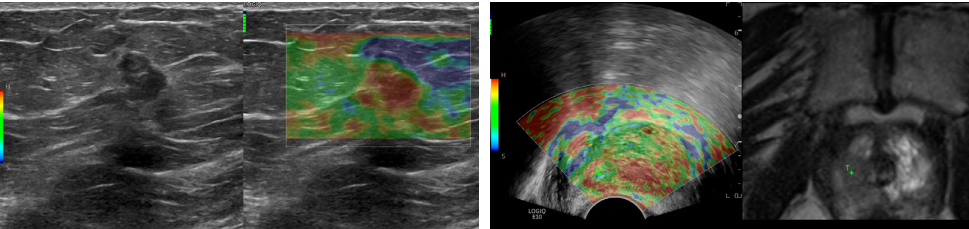

应变式弹性成像:

应变式弹性成像对于组织软硬度的评估,在判断病变性质方面具有重要意义,可应用到浅表组织器官、腹部和盆腔脏器等各个领域。